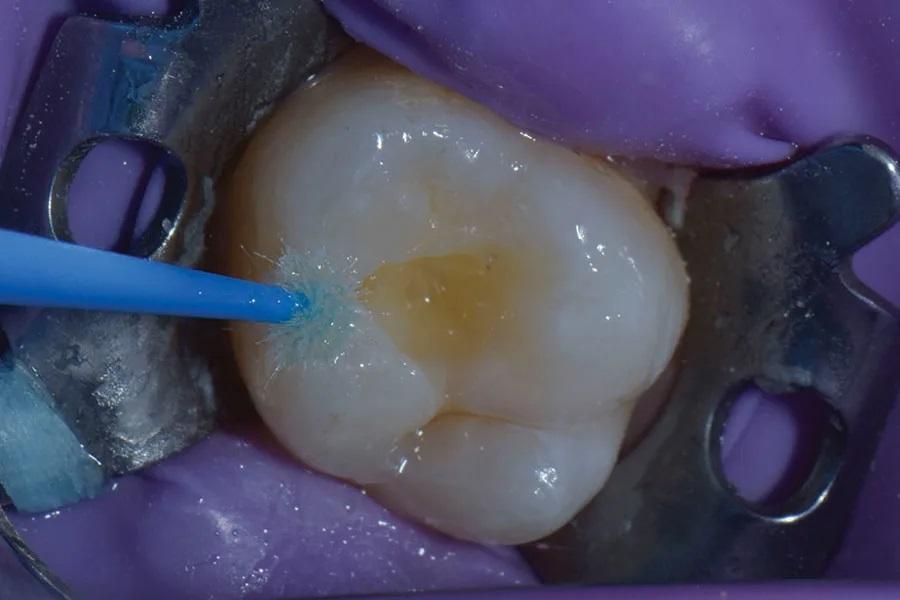

Полость обработана абразивоструйно аппаратом (AquaCare, Velopex International) 29 мкм оксида алюминия в течение 20 секунд для удаления остаточного распада и бактерий. Нанесен протравочный состав (Vococid, VOCO) на 20 секунд по эмали и 10 секунд по дентину с последующим тщательным смыванием (Фото 7). Затем нанесен универсальный адгезив (Futurabond U, VOCO) (Фото 8). После этого внесен один слой текучего композита (Admira Fusion x-base). Финальным слоем использован омнихромный объемно-вносимый жесткий композит (Admira Fusion x-tra packable, VOCO). Полость целенаправленно «переполнена» композитом для приема окклюзионного «штампа» (Фото 9).

Фото 9. После внесения одного слоя текучего композита внесен жесткий объемно-вносимый композит; полость переполнена для приема «штампа».

На окклюзионную поверхность уложена тонкая полоска тефлоновой ленты, чтобы предотвратить прилипание используемого далее «штампа» к композиту (Фото 10). «Штамп» сориентирован относительно зуба и плотно прижат для вдавливания дооперационной окклюзионной топографии в поверхность композита (Фото 11 и Фото 12). Излишки композита легко удалены моделировочным инструментом (OptraSculpt, Ivoclar) (Фото 13). До финальной полимеризации нанесен тинт (Creative Color Honey Yellow, Cosmedent) для эстетической репродукции фиссур (Фото 14), после чего произведена засветка 20 секунд. Окончательная реставрация финишно обработана и отполирована (A.S.A.P. Polishers, Clinician’s Choice).

Фото 11. «Штамп» правильно сориентирован и прижат для переноса дооперационной окклюзионной топографии на композит.